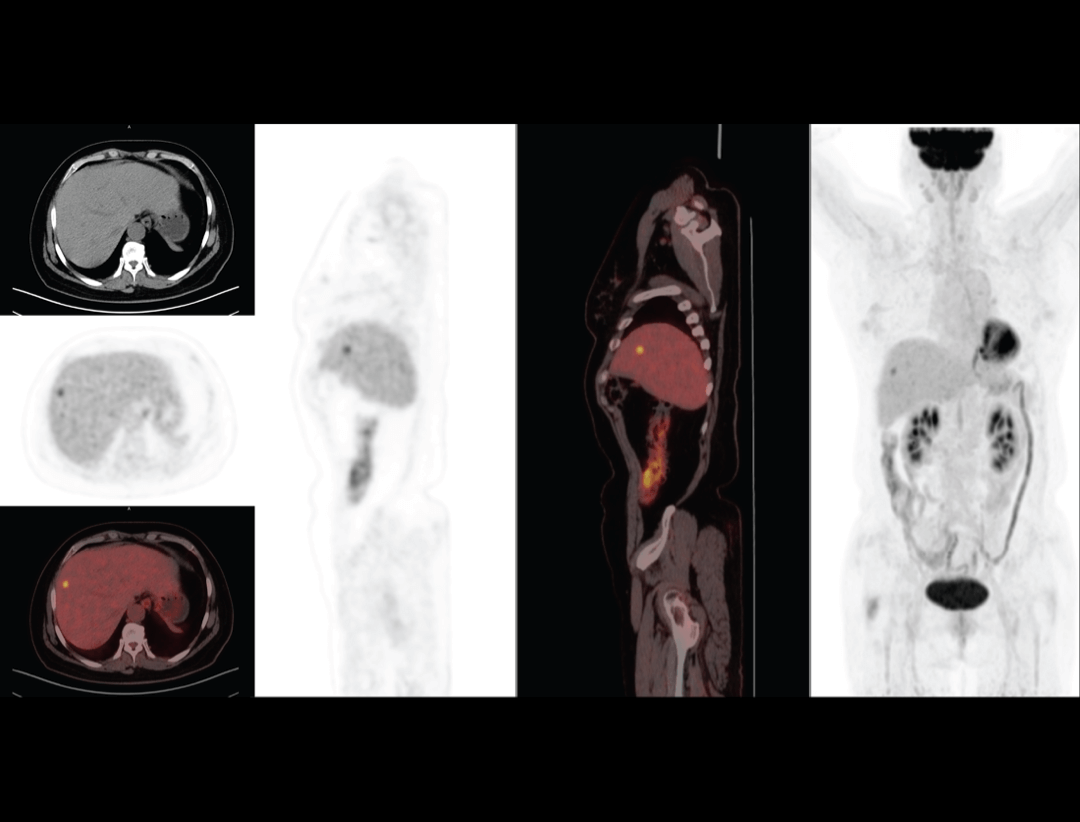

Galerie clinică

Cancer esofagian

Imagistica PET/CT oferă detalii esențiale pentru diagnosticarea și stadializarea cancerului esofagian, permițând evaluarea precisă a extensiei tumorale și monitorizarea răspunsului la tratament.